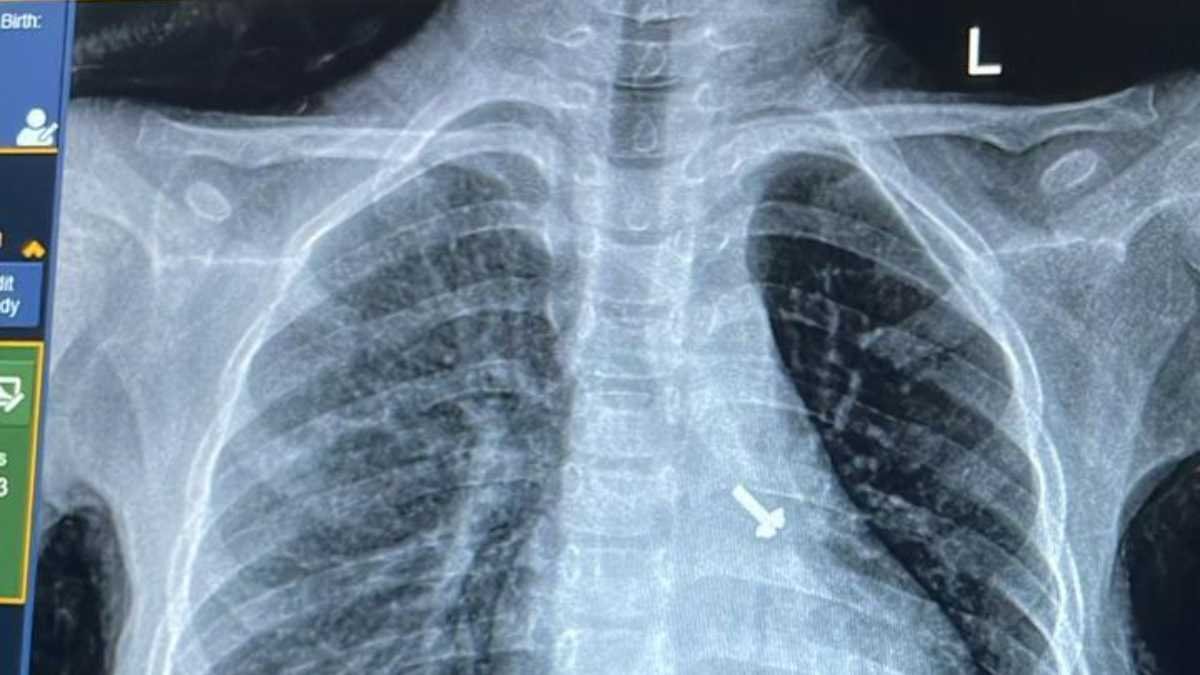

07 वर्ष के बच्चे के फेफड़े में फंसे पेंच को निकालकर एम्स के चिकित्सकों ने दिया जीवनदान

ऋषिकेश: अखिल भारतीय आयुर्विज्ञान संस्थान, ऋषिकेश के पल्मोनरी मेडिसिन विभाग की ओर…